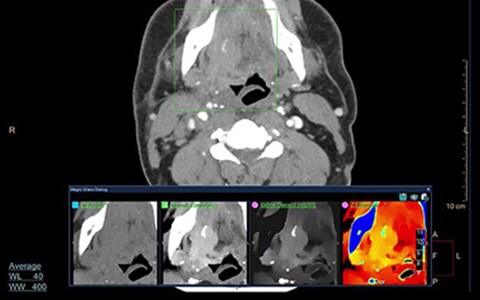

Como mínimo, se necesitan soluciones que ofrezcan calidad de imagen excepcional y rapidez. Sin embargo, para lograr una auténtica seguridad en el diagnóstico se necesitan datos más profundos que proporcionamos con los protocolos de exploración predefinidos, herramientas de interpretación clínica, una visión integral de los pacientes y ayuda para tomar decisiones en función del campo de la genómica, entre otros. Como resultado, se logran procedimientos y flujos de trabajo más estandarizados, imágenes reproducibles de calidad superior y, en última instancia, una mejor atención al paciente.

Vea cómo Philips y CARTI trabajan en forma conjunta para ayudar a los pacientes que reciben tratamientos complejos y cómo el escáner de la TC IQon Spectral ha cambiado la forma en que los pacientes reciben el tratamiento.